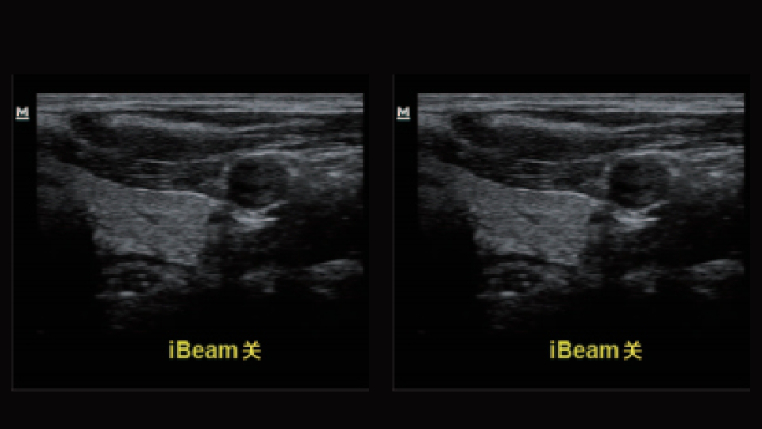

iBeam复合成像

多角度的空间复合成像,在抑制随机噪声和杂波信号的同时提高了空间分辨率,提供更多的诊断信息